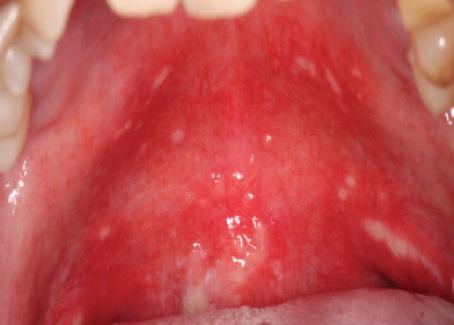

OM initially presents as erythema, with time to onset ranging from two to three weeks and one to two weeks, respectively, after initiation of HNR or CT, and from 3 to 4 days after the first treatment in conditioning regimens.6Brown TJ, Gupta A. Management of Cancer Therapy-Associated Oral Mucositis. JCO Oncol Pract 2020;16(3):103-9. While the mucosal inflammation can remain mild, OM typically develops further to an erosive phase and ulcerative lesions with pseudomembranous surfaces.1Sonis ST. Pathobiology of oral mucositis: novel insights and opportunities. J Support Oncol 2007;5(9 Suppl 4):3-11.,9Haverman TM, Raber-Durlacher JE, Rademacher WM et al. Oral complications in hematopoietic stem cell recipients: the role of inflammation. Mediators Inflamm 2014:378281. doi: 10.1155/2014/378281. When extensive, these lesions cause severe pain and can cause bleeding. OM development begins with the death of basal epithelial cells, which ensues rapidly once HNR or CT commences.1Sonis ST. Pathobiology of oral mucositis: novel insights and opportunities. J Support Oncol 2007;5(9 Suppl 4):3-11. The inflammatory process then involves the release of reactive oxygen species, gene expression and upregulation of multiple inflammatory pathways, and increased production of pro-inflammatory cytokines and other mediators.11Sonis ST, Elting LS, Keefe D et al. Mucositis Study Section of the Multinational Association for Supportive Care in Cancer. International Society for Oral Oncology. Perspectives on cancer therapy-induced mucosal injury: pathogenesis, measurement, epidemiology, and consequences for patients. Cancer 2004;100(Suppl 9):1995-2025.,12Logan RM, Stringer AM, Bowen JM et al. Serum levels of NFkappaB and pro-inflammatory cytokines following administration of mucotoxic drugs. Cancer Biol Ther 2008;77:1139-45. OM lesions typically resolve two to four weeks after cancer therapy is completed. (Figure 1)

Figure 1. OM in patients who received HNR, showing normal, moderate delayed and severe delayed healing (left to right)

Source: Jiang R, Liu Y, Zhang H et al. Distinctive microbiota of delayed healing of oral mucositis after radiotherapy of nasopharyngeal carcinoma. Front Cell Infect Microbiol 2022;12:1070322. Copyright © 2022 Jiang, Liu, Zhang, Chen, Liu, Zeng, Nie, Chen and Tan.